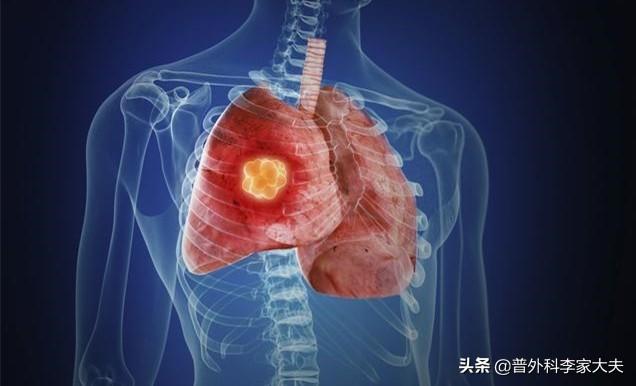

これらの体内信号の出現は、肺癌の可能性が非常に高いことを示している。次のような画像信号が再び現れたら、基本的に肺癌が近づいていることは明らかです。

- 胸部CTは現在、最も効果的な肺癌スクリーニング法である。胸部CT検査で、肺葉徴候、バリ徴候、空胞徴候、気管支像、腫瘍絨毛動脈、血管切断・集塊徴候、胸膜陥凹・引きつれ徴候、偏心腔、すりガラス様病変、肺門腫瘤などの画像信号を伴う肺結節が認められた場合、基本的に肺癌が確定する。

- PET-CT検査:肺の腫瘤が肺がんであるかどうかを判断するのに役立つ。

もちろん、病理学的細胞診や組織診は、肺がんの真の診断のためのゴールドスタンダードである。